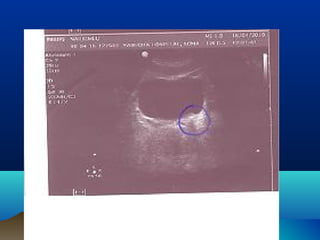

DIAGNOSISDIAGNOSIS

โ€ข ULTRASONOGRAPHY

โ€ข HYDRONEPHROSIS

โ€ข HYDROURETER โ€“ UPPER / LOWER

โ€ข CALCULI โ€“ RENAL / PUJ / URETER

โ€ข PARENCHYMAL THICKNESS

โ€ข URETERIC JET

โ€ข RENAL RESISTIVE INDEX